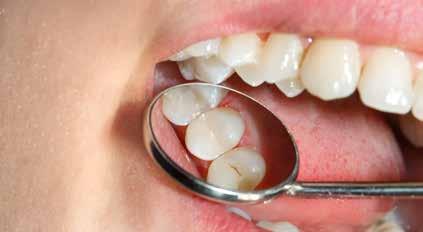

Komposit er mere syreresistent end glasionomer

GASTROØSOFAGEAL REFLUKSSYGDOM (GERD) er en tilstand, hvor ventrikelindhold lejlighedsvis over en længere periode kommer i kontakt med tænder og mundslimhinde. Det er velkendt, at især mavesaftens indhold af saltsyre (HCl) kan forårsage erosion af tandvæv; men også fyldningsmaterialer bliver udsat for HCl i forbindelse med GERD. Brasilianske forskere har i et laboratoriestudie undersøgt, hvordan en række egenskaber for fem forskellige materialer påvirkes efter eksponering for HCl.

Fire forskellige kompositbaserede materialer (Admira Fusion, Activa BioActive-Restorative, Charisma, Filtek Universal Restorative/FU) og et kemisk hærdende glasionomerprodukt (Equia Forte HT Fil/EF) blev udsat for 0,06 M HCl (pH 1,2) ved 37 °C i 30 timer. Efterfølgende blev prøverne analyseret for overfladeruhed, ruhedsprofil, overfladetab, mikrohårdhed og glans (gloss) og sammenlignet med tilsvarende prøver, der ikke var blevet eksponeret for HCl.

Ingen af kompositmaterialerne mistede mikrohårdhed efter syrepåvirkningen. Kompositmaterialerne blev gennemgående kun i ringe grad påvirket af syreeksponeringen. Filtek klarede sig lidt bedre end de øvrige kompositter, idet produktet efter eksponeringen havde laveste overfladeruhed og ruhedsprofil og den højeste glans. Derimod lå Equia Forte højest på parametrene overfladeruhed, ruhedsprofil og overfladetab og lavest på glans.

Forfatterne konkluderer, at HCl kun havde minimal effekt på kompositmaterialerne, men at glasionomercement tilsyneladende ikke er et velegnet restaureringsmateriale til patienter med GERD.